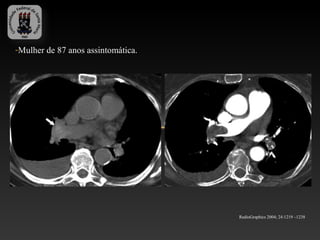

-Mulher de 87 anos assintomática.

RadioGraphics 2004; 24:1219 –1238